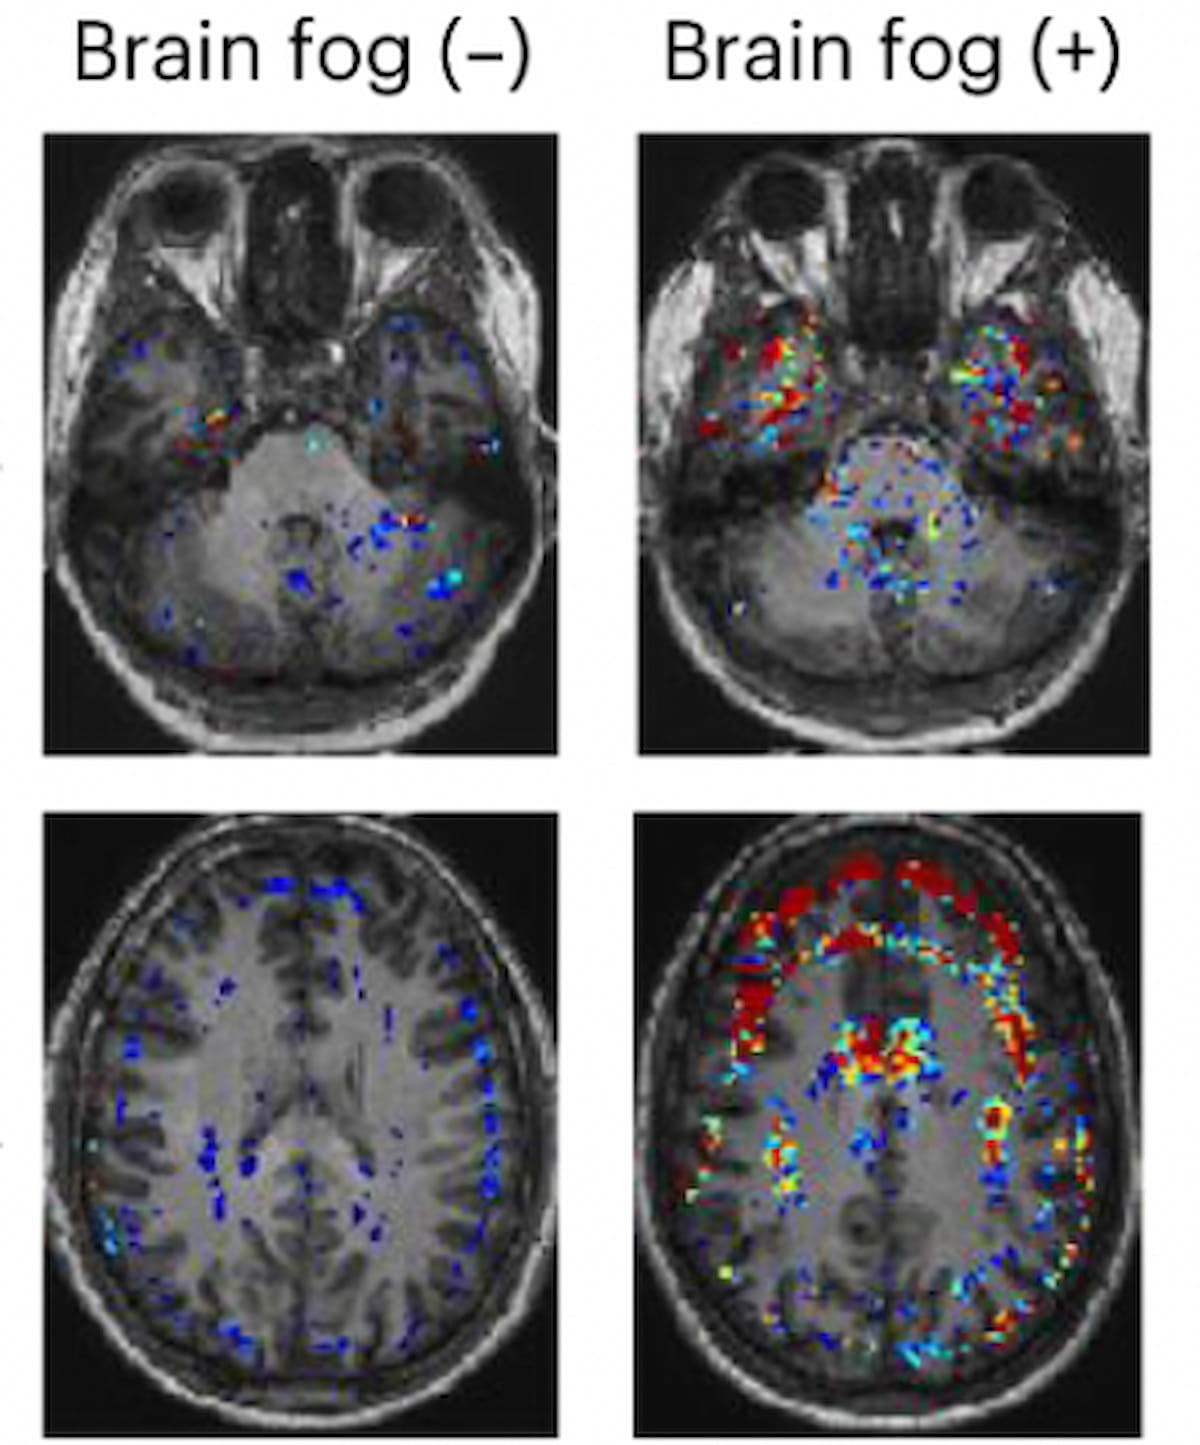

In a recent interview, Alexander Rau, M.D., discussed emerging research, presented at the recent RSNA conference, that shows the capability of diffusion microstructural imaging to differentiate subtle shifts in microstructural gray matter associated with common symptomatology of long Covid.